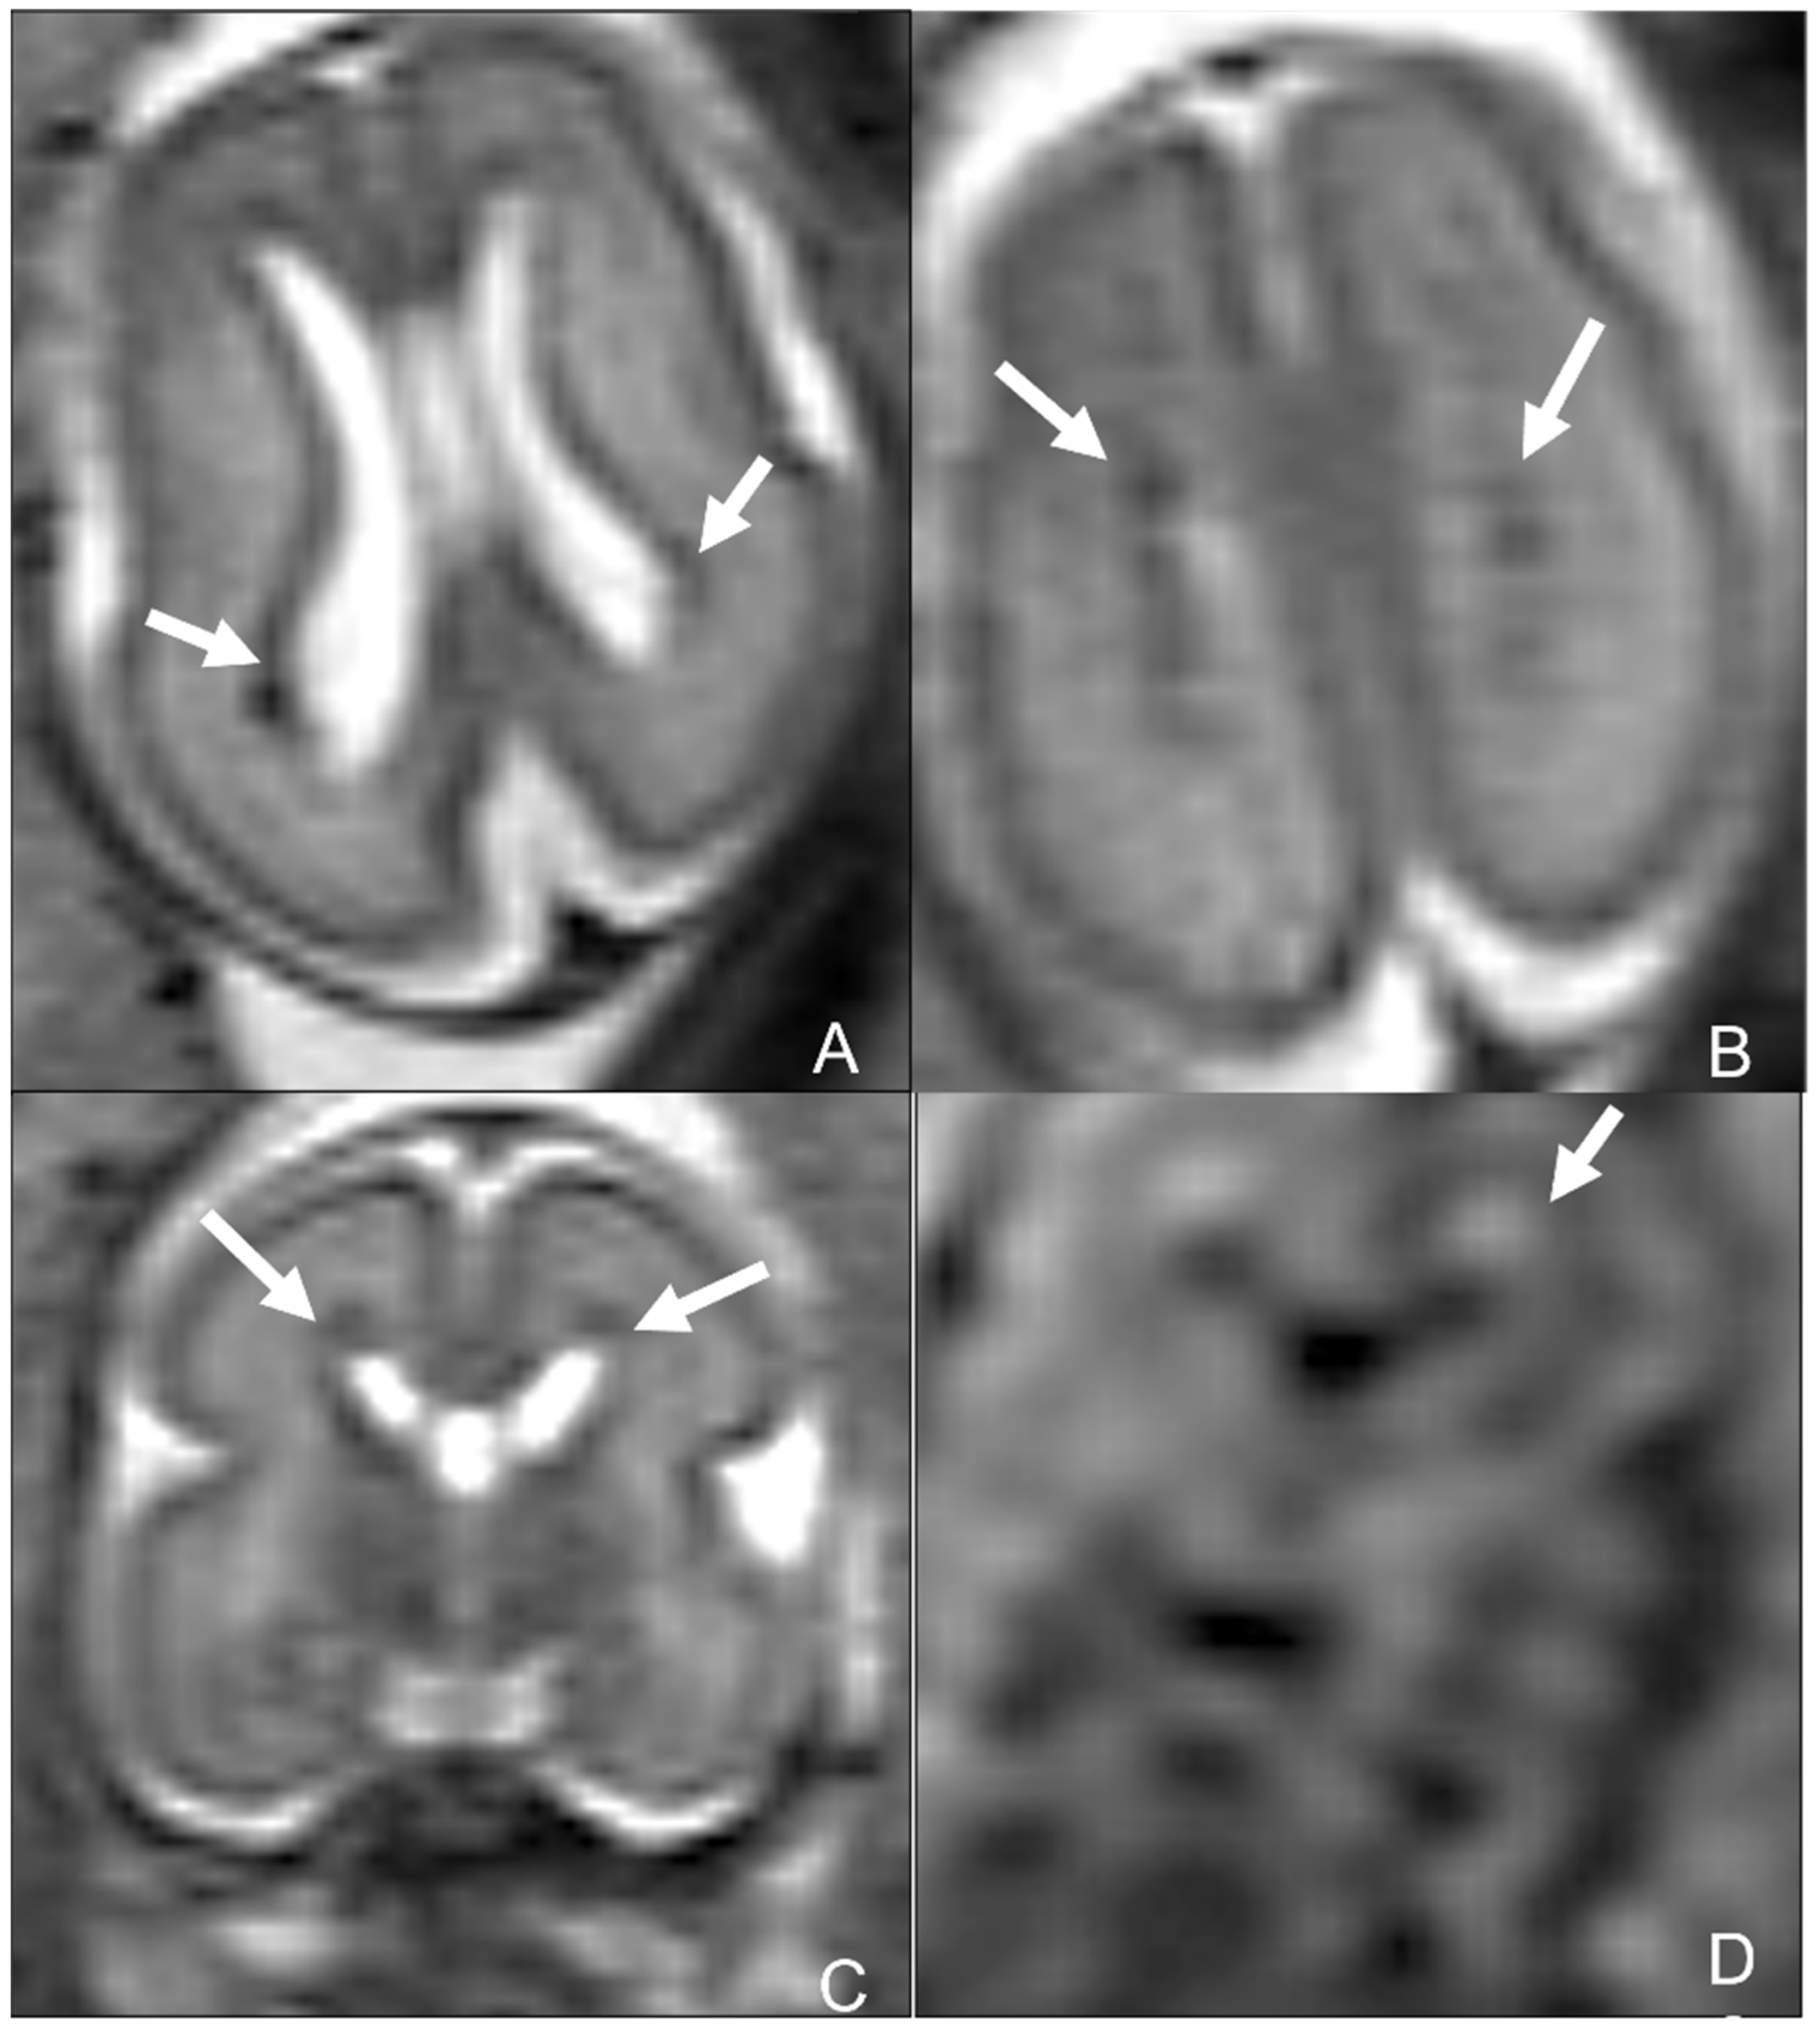

- Schulert, G.S.; Walsh, W.F.; Weitkamp, J.-H. Polymicrogyria and congenital parvovirus b19 infection. AJP Rep. 2011, 1, 105–110. [Google Scholar] [CrossRef] [PubMed]

- Pistorius, L.R.; Smal, J.; De Haan, T.R.; Page-Christiaens, G.C.; Verboon-Maciolek, M.; Oepkes, D.; De Vries, L.S. Disturbance of cerebral neuronal migration following congenital parvovirus B19 infection. Fetal Diagn. Ther. 2008, 24, 491–494. [Google Scholar] [CrossRef]